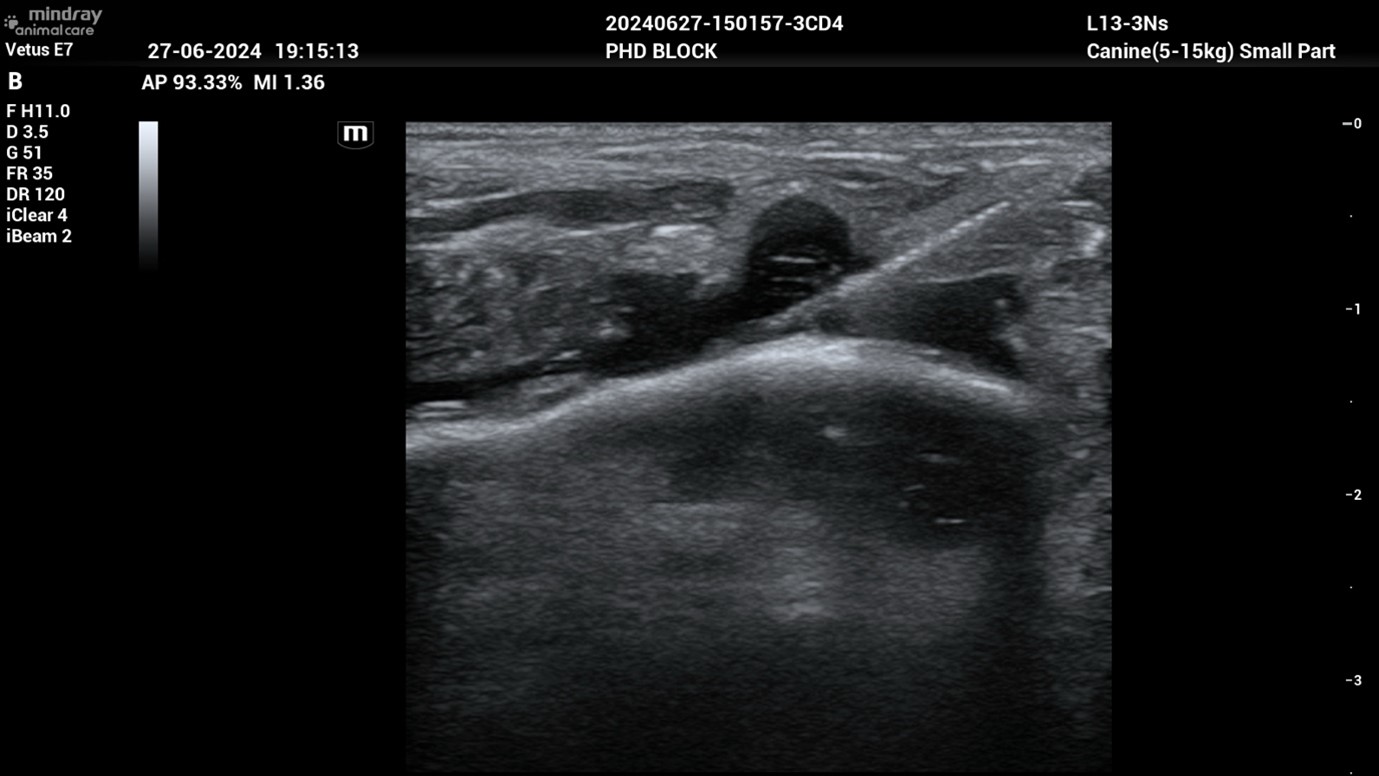

Ja, der PHD-Block (Pericapsular Hip Desensitisation) ist eine wirksame Methode zur Schmerzbehandlung bei Hunden mit Hüftgelenksproblemen, insbesondere Osteoarthritis oder Hüftdysplasie. Dieser Block wird mit Ultraschall durchgeführt und hat zum Ziel, die Schmerzübertragung über bestimmte Nervenäste des oberen Gesässnervs gezielt zu unterbrechen. Diese Nerven versorgen insbesondere den vorderen und hinteren Bereich der Hüftgelenkskapsel, der für die Schmerzwahrnehmung bei Hüfterkrankungen entscheidend ist. Ein Lokalanästhetikum sowie ein langwirksames Schmerzmittel werden gezielt in die Nähe dieser Nerven injiziert, um die Schmerzleitung vorübergehend zu blockieren. In der Praxis bietet dieser Block eine wichtige Option zur Schmerzkontrolle, die dazu beitragen kann, die Lebensqualität von Hunden mit schwer behandelbaren Hüfterkrankungen zu verbessern. Es ist wichtig, dass solche Verfahren von erfahrenen Veterinäranästhesisten durchgeführt werden, um die Sicherheit und Wirksamkeit der Behandlung zu gewährleisten. Wir bieten diese Option am Universitären Tierspital an.